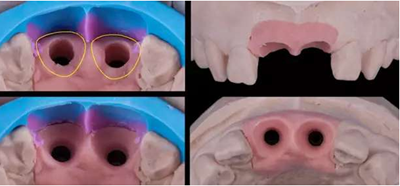

11,21 ASC 全瓷基臺(tái)一體冠蠟型

Asc基臺(tái)數(shù)字化設(shè)計(jì)

螺絲通道改變25°

通過改變螺絲通道角度,調(diào)整螺絲開口位置